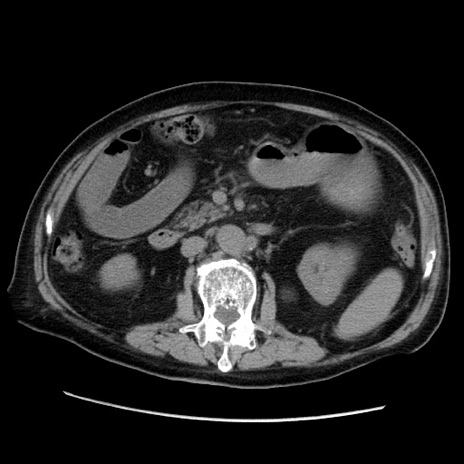

冠状断像

【症例】70歳代男性

【主訴】腹痛

【現病歴】肝硬変・肝細胞癌にてかかりつけの方。約9時間前に食後より腹痛出現。症状が徐々に増悪し、嘔吐出現したため来院。

【既往歴】肝硬変、肝細胞癌(RFA、TACE後)

【身体所見】意識清明、表情苦悶様、BT 36℃、BP 129/78mmHg、P 88bpm、SpO2 97%(RA)、右上腹部から心窩部にかけて圧痛あり、反跳痛なし、筋性防御あり。

【データ】WBC 5800、CRP 0.16